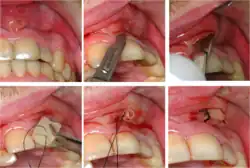

Plastic wedge to identify pain on biting from a fractured tooth Plastic wedge to identify pain on biting from a fractured tooth

Transillumination demonstrating fracture Transillumination demonstrating fracture

Decay (green) with apical abscess (blue) Decay (green) with apical abscess (blue)

Gutta-percha point indicating abscess origin Gutta-percha point indicating abscess origin